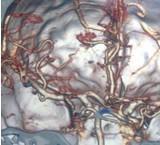

颅内动脉瘤

628健康网为您分享有关颅内动脉瘤的症状,颅内动脉瘤的治疗方法,颅内动脉瘤的预防知识,颅内动脉瘤的症状图片,颅内动脉瘤...

-

大脑大静脉瘤

小儿脑血管畸形

628健康网为您分享有关小儿脑血管畸形的症状,小儿脑血管畸形的治疗方法,小儿脑血管畸形的预防知识,小儿脑血管畸形的症状...

小儿烟雾病

628健康网为您分享有关小儿烟雾病的症状,小儿烟雾病的治疗方法,小儿烟雾病的预防知识,小儿烟雾病的症状图片,小儿烟雾病...

脑动静脉畸形

628健康网为您分享有关脑动静脉畸形的症状,脑动静脉畸形的治疗方法,脑动静脉畸形的预防知识,脑动静脉畸形的症状图片,脑...